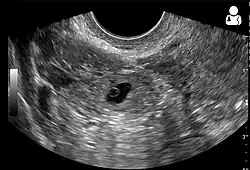

Transvaginal ultrasonography

An ultrasound showing a gestational sac with the fetal heart in the fallopian tube has a very high specificity for ectopic pregnancy. It involves a long, thin transducer, covered with the conducting gel and a plastic/latex sheath and inserted into the vagina.[38] Transvaginal ultrasonography has a sensitivity of at least 90% for ectopic pregnancy.[5] The diagnostic ultrasonographic finding in ectopic pregnancy is an adnexal mass that moves separately from the ovary. In around 60% of cases, it is an inhomogeneous or a noncystic adnexal mass, sometimes known as the "blob sign". It is generally spherical, but a more tubular appearance may be seen in the case of hematosalpinx. This sign has been estimated to have a sensitivity of 84% and a specificity of 99% in diagnosing ectopic pregnancy.[5] In the study estimating these values, the blob sign had a positive predictive value of 96% and a negative predictive value of 95%.[5] The visualization of an empty extrauterine gestational sac is sometimes known as the "bagel sign", and is present in around 20% of cases.[5] In another 20% of cases, there is visualization of a gestational sac containing a yolk sac or an embryo.[5] Ectopic pregnancies where there is visualization of cardiac activity are sometimes termed "viable ectopic".[5]

A pregnancy not in the uterus[39]